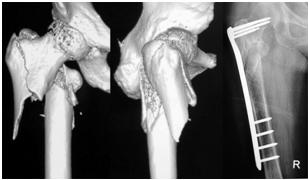

图为:85岁,股骨粗隆部粉碎骨折,微创置入LISS,术后 3个月骨折愈合

85 years old female, completely displaced fracture of proximal

right femur. Fracture healed 3 months after reverse femoral LISS fixation.